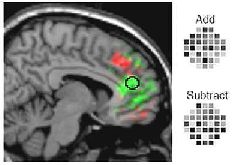

Para executar a “leitura da mente”, os cientistas pediram que voluntários optassem por uma de duas tarefas – somar ou subtrair números – se concentrassem na decisão e, depois, a executassem, ao ver os algarismos surgindo numa tela. Haynes e seus colegas afirmam que foram capazes de adivinhar a intenção dos voluntários com 70% de precisão, apenas analisando a atividade cerebral – antes mesmo que os números aparecessem.

Os voluntários escolheram a operação matemática em segredo, sem saber quais os números que seriam apresentados. Esse protocolo foi adotado para separar a atividade mental da tomada de decisão da de, efetivamente, fazer a conta, evitando erros de interpretação nos sinais captados pela ressonância magnética.